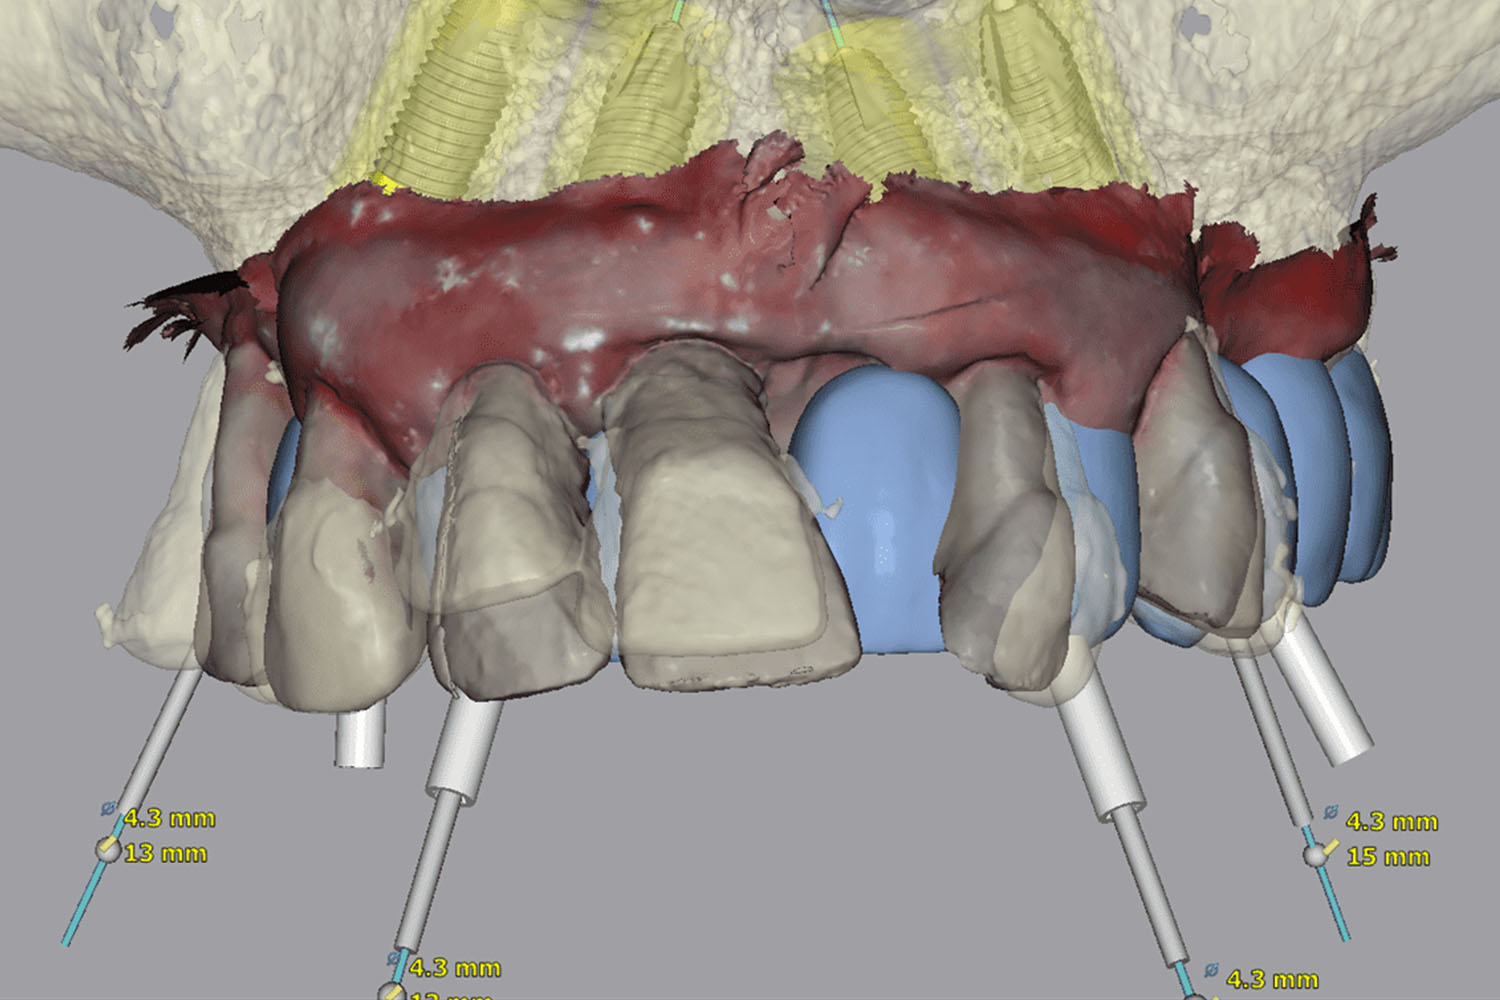

Precizno planiranje uz 3D dijagnostiku

Koristimo suvremenu 3D CBCT dijagnostiku, digitalne otiske i virtualno planiranje implantata kako bismo terapiju planirali precizno i sigurno.

Tijekom druge posjete izvodi se All-on-4® zahvat. Ako je dogovorena digitalna All-on-4® metoda, implantati se ugrađuju pomoću dinamičke navigacije, a odmah nakon zahvata izrađuje se privremeni most.